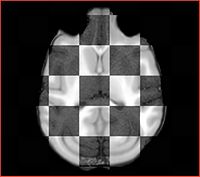

• Current effort: register rhesus atlas to vervet subjects. Preliminary results: overlay of the Gucci manual 3-class segmentation with the rhesus atlas post-affine before bspline registration (first row) and multilevel registration including bspline using BRAINSFit (second row), and another slice from the same volume, not so successful (third row).

Rhesus has the frontal part bent down, and registration does not seem to capture this sufficiently. More experimentation is needed.

Also note the differences in the gyration patterns post-registration.